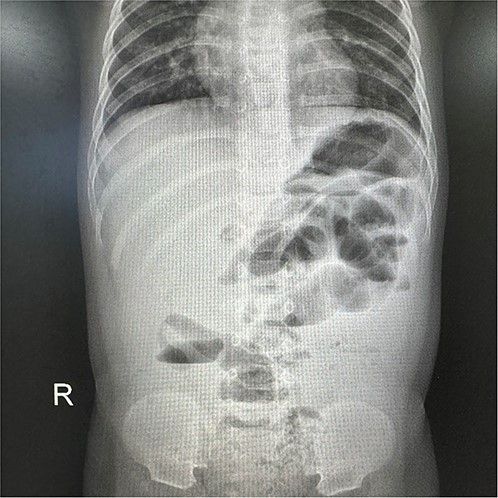

After admission,the patient underwent a physical examination revealed abdominal distension accompanied by tenderness and localized guarding in the right lower quadrant. Abdominal X-ray revealed partial small intestinal pneumatosis expansion in the left middle upper abdomen and right middle lower abdomen, alongside multiple air-fluid levels, suggestive of a potential ileus (Fig. 1). Laboratory tests showed a white blood cell count of 3.99 × 109/L and a C-reactive protein level of 154.33 mg/L.

X-ray revealed partial small intestinal pneumatosis expansion alongside multiple air-fluid levels.